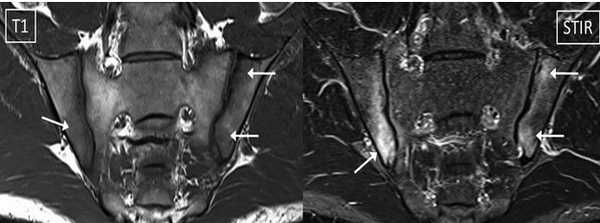

МРТ-признаки остеомиелита лонных костей: расширение сочленения и скопление жидкости с формированием параартикулярных затеков (длинные стрелки), разрастание грануляционной ткани (короткие стрелки), Т2-ВИ, аксиальная (а) и коронарная (в) плоскости

МРТ крестцово-подвздошных суставов - типичный воспалительный сакроилеит при аксиальном спондилоартрите (стрелки)